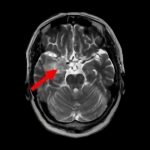

断層撮影